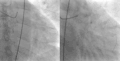

Angiograma coronario, con un vídeo a la izquierda que muestra una estenosis crítica (95%) de la LAD proximal en un paciente con síndrome de Wellens; El vídeo de la derecha muestra al mismo paciente después de la reperfusión .- EKG en un paciente con síndrome de Wellens cuando tiene dolor en el pecho